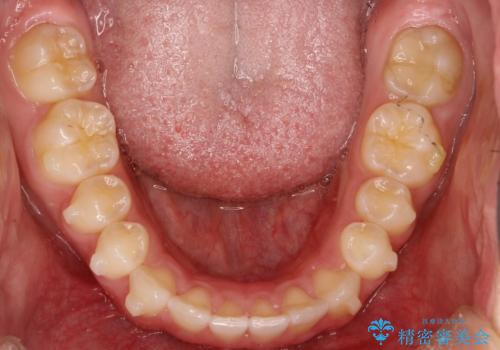

前歯の隙間がきになる インビザラインですきっ歯の治療

インビザラインにて矯正治療を行いました。

しっかり使っていただけたので、スムーズに治療を終了することができました。